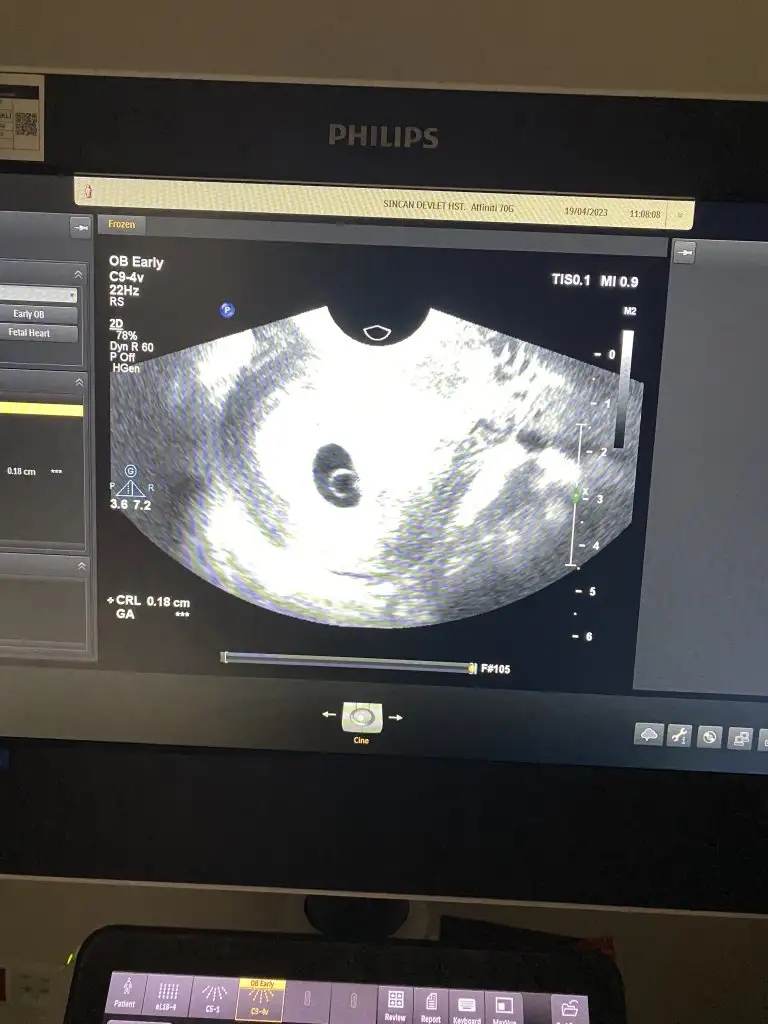

Merhaba kızlar doktordan geldim 🫣

İlk beni çok korkuttu kalbime inme inecekti o derece heyecanlandım

Karindan baktı çok karışık göremedim falan dedi kese nerde derken kanama alanından dolayı sanırım dedi

neyse bende alt ultrason istedim sanırım bos keseden şüphe etti

Başka doktorun vajinal ultrason kısmına geçtik (devlet hastanesi olduğu için)

Orada kese gördük uygulamaya göre 6.hafta ama ultrasona göre 5.haftalarda bu kapatır ilerde fazla önemsemiyoruz dedi

Yolk gözükünce kalp atışınida duyduk daha yeni yeni yavaş dedi çok erken ama iyi dedi yani 5.haftalarda duymuş oldum🥰😍🥹

Kontrol için bir ay sonra dedi çok uzun değil mi ya

🤔 kanama alanım devam ama pedi dolduracak kadar olursa hemen gel dedi

Eklentiler

• IMG_4674.webp

IMG_4674.webp

37 KB · Görüntüleme: 50